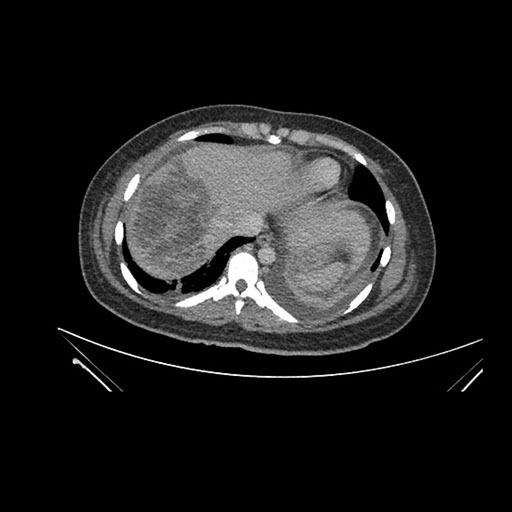

Imaging Analysis

Look through the patient's CT scan to identify any areas of concern for the necessary procedure.

Axial Arterial